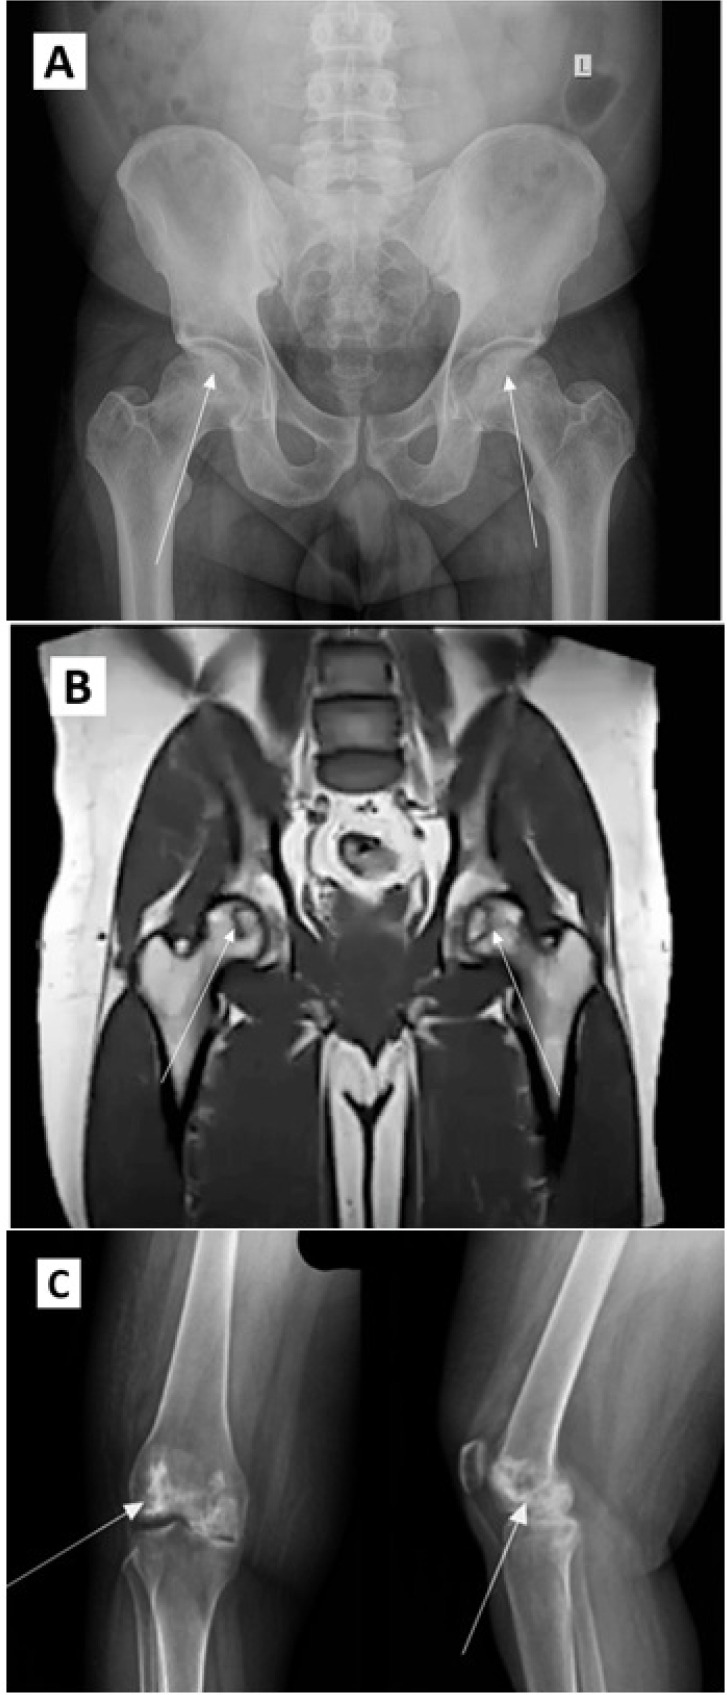

Steroids are used in management of coronavirus disease 2019 (COVID-19) patients with severe illness and their use has been demonstrated to decrease mortality. Although life-saving, steroids are well documented as risk factors for osteonecrosis. Osteonecrosis of the hip can be debilitating and surgery may be required to improve the quality of life. With the increasing number of COVID-19 cases, osteonecrosis of the hip and other joints resulting from steroid use is expected to show a sharp rise in the coming years. In this review we discuss the association between steroids and osteonecrosis, indications for steroid therapy in COVID-19 patients, and incidence, diagnosis, and treatment of osteonecrosis secondary to steroids in COVID-19.